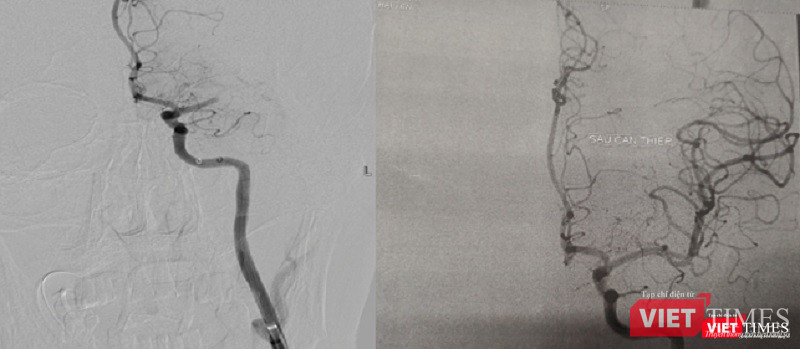

![]() |

| Hình ảnh động mạch não trước và sau khi hút huyết khối |

Ngay lập tức, hai cuộc phẫu thuật được thực hiện cùng lúc để cấp cứu bệnh nhân. Hai ekíp bác sĩ can thiệp thần kinh và can thiệp mạch vành nhanh chóng thống nhất phương án xử lý và quyết định thứ tự các kíp can thiệp, bắt đầu hút huyết khối để tái thông dòng chảy trên hệ mạch máu não trước, sau đó tiến hành can thiệp đặt stent động mạch vành cho bệnh nhân.